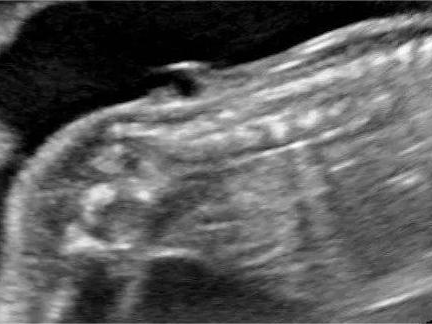

(2)检查内容

主要观察能显示的胎儿重要器官的形态结构,包括:胎儿的小脑、侧脑室、上唇部、脊柱、严重的腹壁缺损胸腹脏器外翻、肾脏、胃泡、膀胱、股骨肱骨胫腓骨尺桡骨、四腔心等。在妊娠期间,每位胎儿都要做32~39个切面检查。

神经管缺陷是一组严重的先天性疾病,如唇裂、腭裂、脊柱裂等,会严重影响孩子出生后的生活质量。